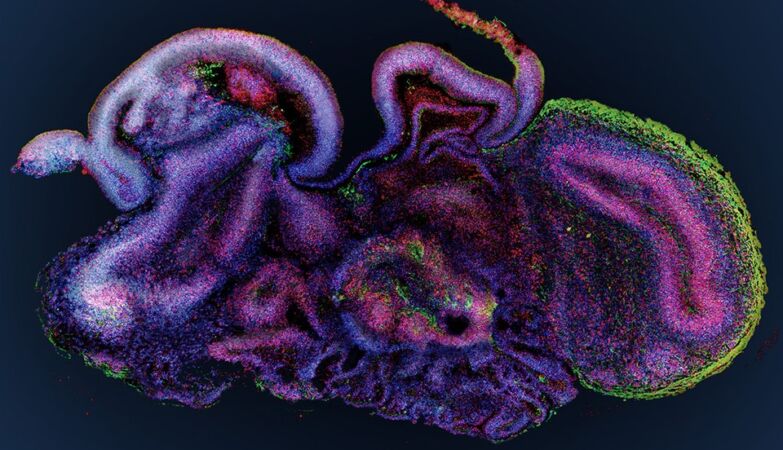

Juergen Knoblich

organoid brain

The organoids were not grown from human tissue, but rather from mouse stem cellscultivated to form small clusters of cortical tissue capable of neuronal signaling.

These organoids were not complex enough to something approaching thought or consciousness, but they were able to send and receive electrical signalsand its internal connections could change in response to external stimulation.